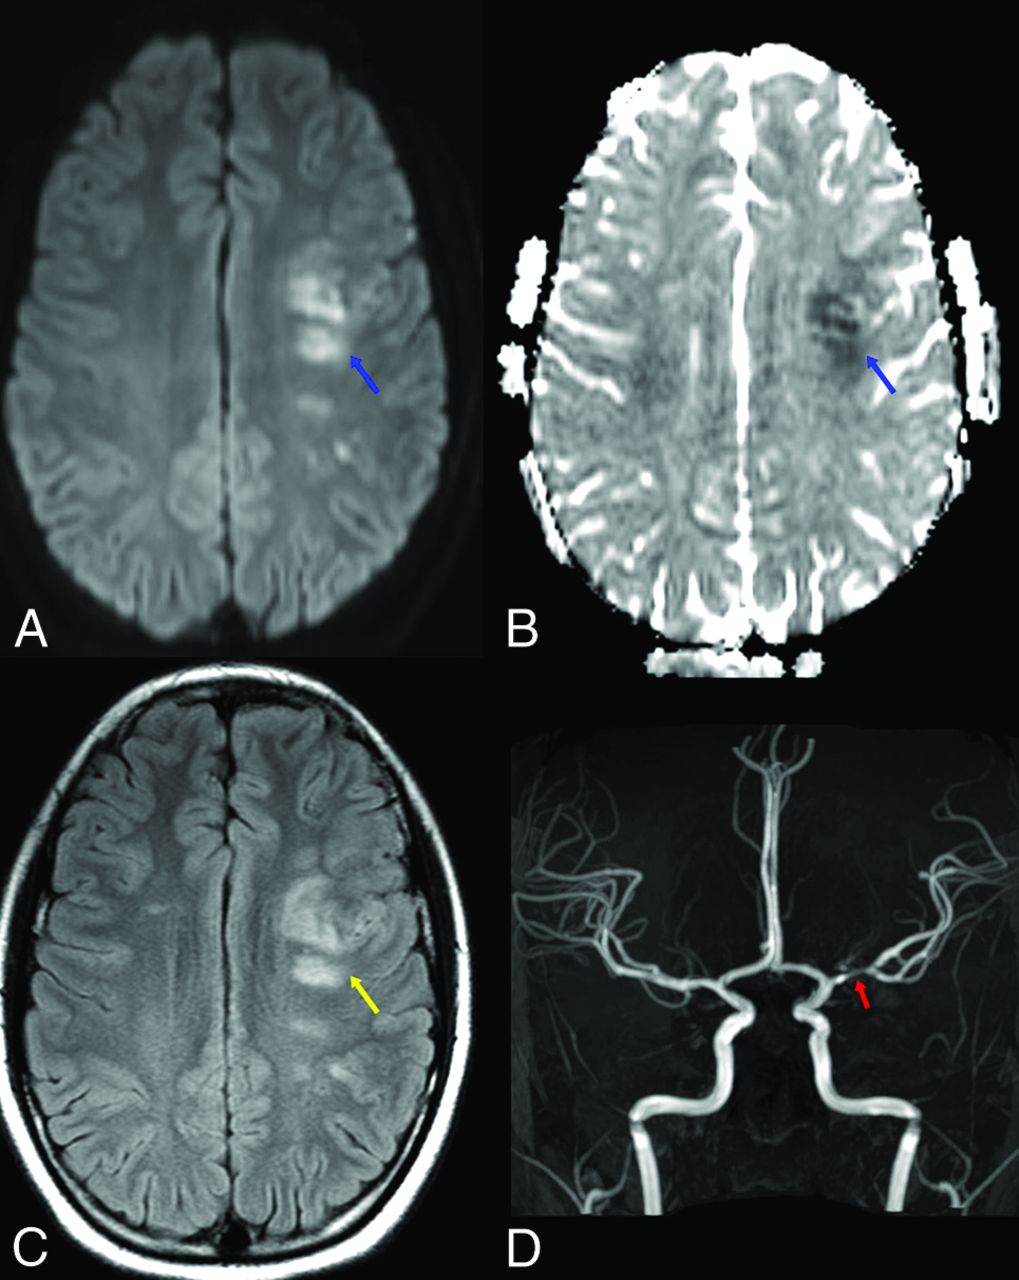

Vessel wall enhancement within the M1 left MCA. Vessel wall imaging targeted to the left middle cerebral artery with axial pre- (A) and postcontrast (D) 3D T1 volume isotropic turbo spin-echo acquisition sequences, with reformatted coronal images; B and E, respectively). Pre- (C) and postcontrast (F) reformatted sagittal images en face to the M1 left middle cerebral artery at the level of the blue and yellow arrows, respectively. There is wall thickening (blue arrow) and marked concentric contrast enhancement of the M1 left middle cerebral artery at the segment of stenosis (yellow arrows). The imaging findings, in conjunction with the clinical history, were consistent with FCA-inflammatory type.